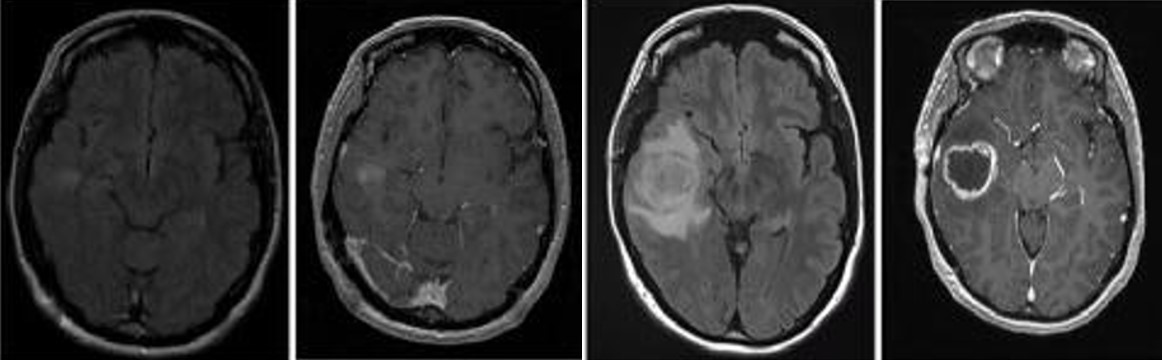

胶质母细胞瘤(Glioblastoma , GBM)是中枢神经系统中比较常见的神经上皮肿瘤,是恶性程度最高的原发性脑肿瘤也是最致命的实体瘤,被世界卫生组织归类为Ⅳ级胶质瘤。GBM 预后差,被诊断后的平均中位生存期为 14个月,其5年生存率为 5%。尽管目前在外科手术,放化疗等医学治疗手段取得了不错的进展,但在延长患者的生存期上仍未取得突破。因此,目前迫切需要筛选鉴定出有效的GBM生物标记物,探索GBM的治疗靶标并解析GBM的发病机理,为GBM的早期诊断及预后评估提供新策略以延缓患者的生存期。

崔红娟教授团队就GBM标志物的筛查、鉴定以及如何管控EGFR在GBM的表达开展了深入研究。首先, GBM患者组织的免疫组化病理检测以及生物信息学分析发现一种能够参与异染色质形成的H3组蛋白甲基化阅读器CBX3(Chromobox 3)在GBM患者中异常高表达,并且与GBM的预后和恶性分级密切相关。功能检测表明了CBX3 在体外和体内显著促进 GBM 细胞的增殖、侵袭和肿瘤发生。从机制上来说,我们通过Ch-IP和Co-IP等一系列生物技术实验证明了CBX3促进GBM 的恶性进展是EGFR 依赖性的,并且进一步揭示了GBM患者发病机理的一条全新的信号通路CBX3-PARK2/STUB1-EGFR。该研究不仅丰富了GBM表观遗传学的研究,也为该信号通路作为GBM潜在治疗靶点的可行性提供了坚实的依据。best365英国在线体育官网2020级博士研究生彭文为第一作者,崔红娟教授为该论文的通讯作者。该研究得到了重庆市自然科学基金和重庆市博士生科研创新项目的支持。